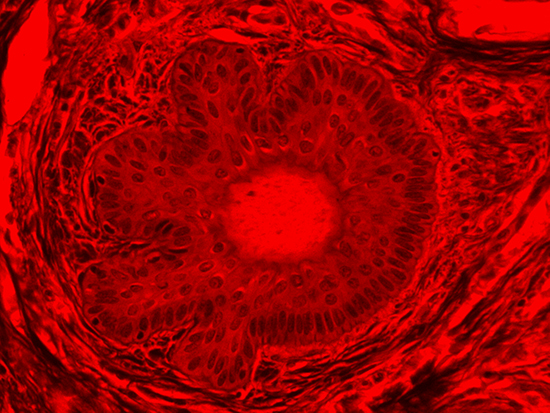

Masson's trichrome stain is incredibly effective in differentiating cells and their components from the surrounding connective tissues. One of the most common stain types, which has been used on the dermal tissue sample seen in the images within this article, yields a number of colors where cell nuclei appear dark red, collagen and other tissues appear green or blue, and cell cylasm appear red/purple (Jones, 2010). These stains have been imaged under brightfield and darkfield illumination, and then again with specific filters to selectively focus on the cellular constituents of the epidermis. The primary application for the epidermal trichrome stains is differentiating healthy collagen and muscles from connective tissues onset with tumorigenesis. Typically the tumors proliferate from muscle cells and fibroblasts deep in the dermal tissue (Blitterswijk, 2010).

Figure 4: Brightfield Image of Dermal Tissue filtered with Red

When comparing Figure 3 with Figure 4, there is once again a significant visual difference. The most obvious feature is the change in color from green to red due to a different hardcoated filter being positioned in the optical path. The less obvious difference is the varying contrast levels caused by the filters at specific regions of the dermal tissue. For example, Figure 3 exhibits a distinct ring at the central region of the cell with additional matter within. In Figure 4, the ring is extremely faint and the internal matter is not visible. With that said, the cell and surrounding dense materials are more evident in Figure 3, whereas the muscle fibers and collagen are more pronounced in Figure 4.